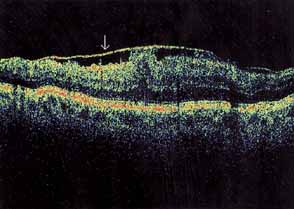

Optical coherence tomography or OCT is a relatively new tool used to diagnose macular lesions. It provides a unique view of the vitreoretinal architecture. OCT is particularly useful in diagnosing lamellar holes. With improvements in resolution and more widespread use, OCT will lead to new advances in the diagnosis and pathogenesis of macular holes (Fig. 2).

|